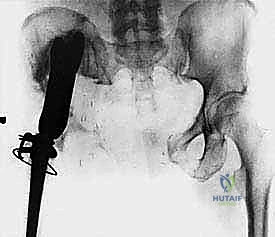

- Fluoroscopy: The C-arm will be draped and positioned to allow for intraoperative AP and oblique views of the pelvis without repositioning the patient. We've ensured clear access to the entire operative field.

- Initial Cuts: "We'll start with the iliac wing osteotomy. Use a large oscillating saw or Gigli saw, under constant visual and fluoroscopic guidance, to make the superior cut through the ilium, staying well clear of the sacroiliac joint."

* Acetabular Cuts: "Next, we'll address the periacetabular cuts. This requires careful planning to maintain stability for reconstruction. We'll use a combination of osteotomes and a small oscillating saw. The pubic ramus will be cut anteriorly, and the ischium posteriorly. Ensure adequate bone stock for reconstruction."